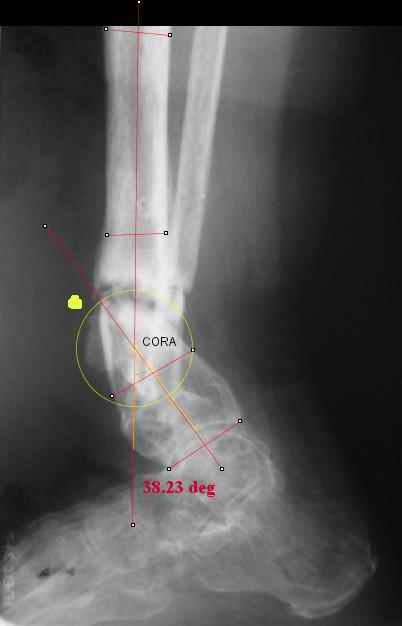

TDVC> I played with your image using some orthopedic software

TDVC> we have been developing for digital image analysis.

TDVC> a correction around the CORA through the old # will restore

TDVC> alignment without much translation.

Maybe my "embedded software" is obsolete but it hints me to place hinges at the yellow point - this must result with alignment and some lengthening without translation. What do you think?

I think that if you locate the hinge at that site and then you rotate the foot about this point with out distraction you will be perfectly lined up. If you distract in the axis of the proximal tibia then rotate, it should still work (the hinge should still be located in the mid tibial axis). But, if you distract out of that axis then you will get translation. Does that make sense?

I looked at your image. I presume your yellow marker is the hinge axis? I think this should be at the CORA.